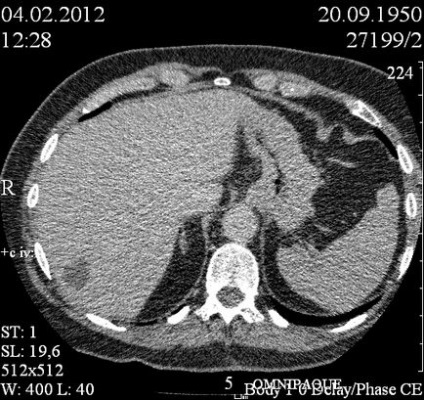

Lép: Kontúrok egyenlő, pontos. Méretek: 9,5x3,4 cm.

Szerkezet: homogén közegben echogenicitást az alsó felében vannak meghatározva izoehogennoe képződését 1,8h1,3 cm 1,0h0,9 cm keréktárcsák alsó pólus - hypoechogenic részét 1,1h1,2 cm.

Kialakítása előtt a kontraszt tette rosszul, sűrűsége körülbelül 27 ed.N. Az artériás fázisa kontraszt nem halmozódnak, kivéve az egyik kamrában, amely felhalmozódik (Contrast, hogy ez a kandalló nem egyértelműen vizuliziruetsya feltehetően izodensiven).

A parenchymás felhalmozódnak fáziskontraszt. Képződmények a parenchyma csak körülbelül 6, beleértve a subcapsularis helyen. A szerkezet a homogén képződmények, kerek alakú, tiszta kontúrokkal.

5 perc elteltével Introducion kontraszt képződését izodensivny lép parenchyma. Egyes elszigetelt retroperitoneális nyirokcsomó méretig 6 mm.

OGC is végzett CT. Talált coelomic ciszta a szívburok. Mediasztinális nyirokcsomók vannak a nem kibővült. Becsült következtetés: multifokális lép limfóma, vagy metasztázis a lépben.

5 perc elteltével az adagolás után a kontraszt: